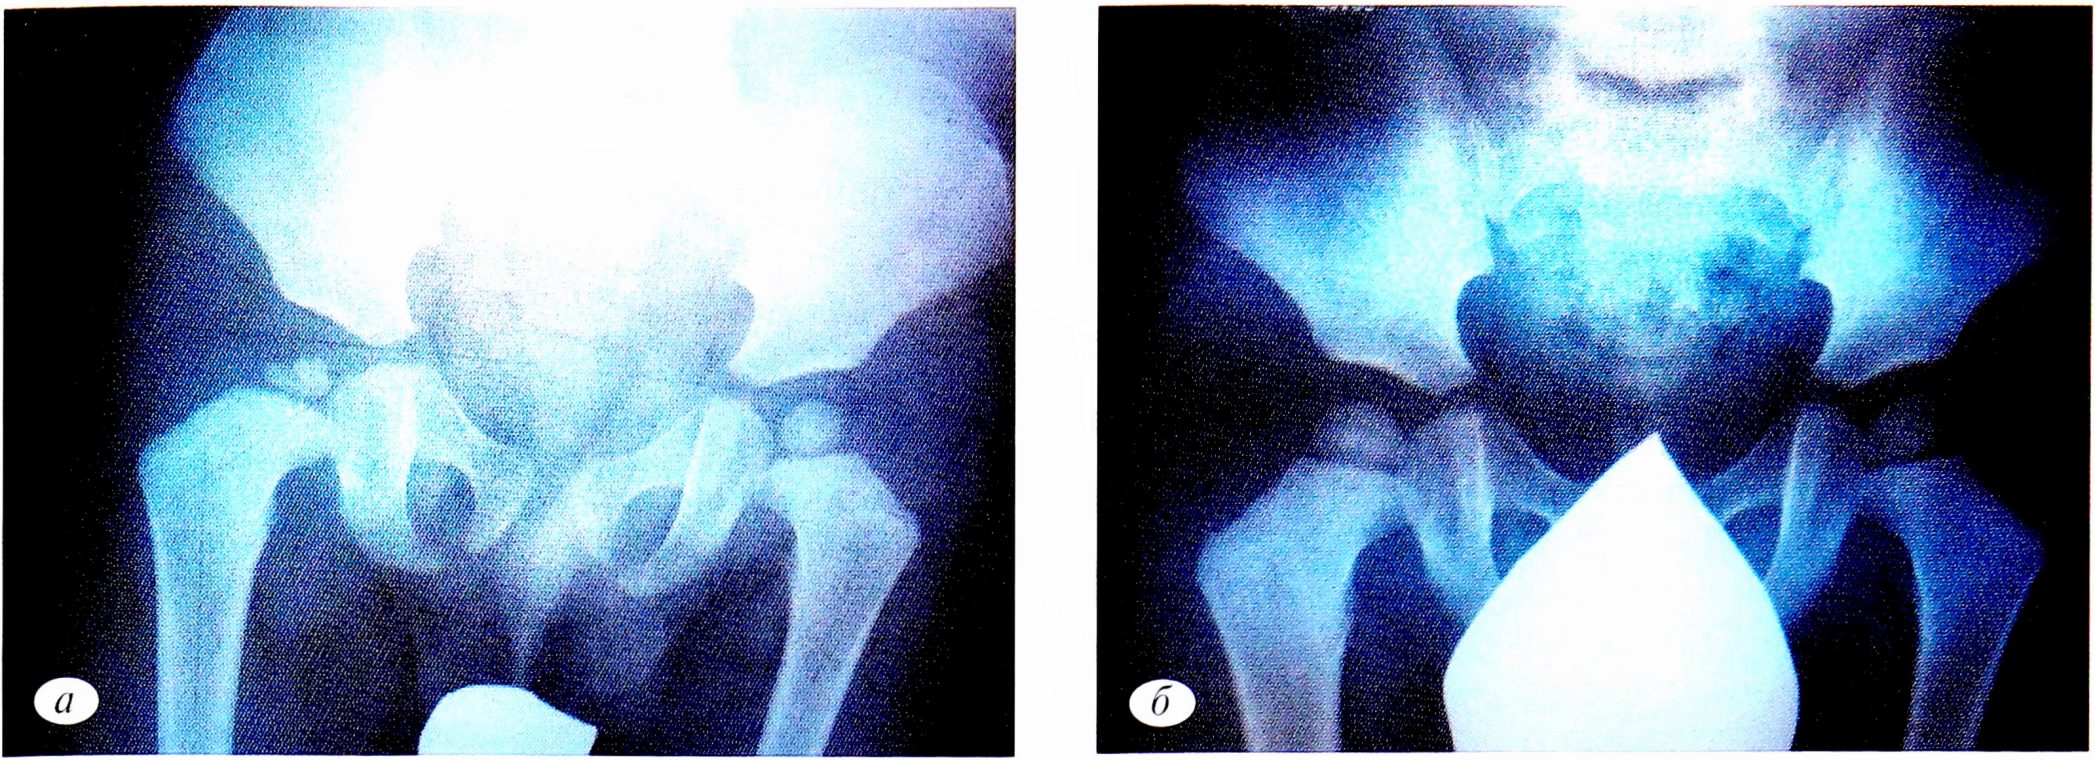

Из истории болезни: дисплазия ТБС выявлена в возрасте 2 мес при УЗИ. Лечение: разведение ТБС подушкой Фрейка (16 см), расслабляющий массаж (10 процедур), электрофорез 3% СаС12 на ТБС (10 процедур), ЛФК на разведение в ТБС. На контрольном УЗИ ТБС в 3,5 мес определялись признаки нормализации углов (α — более 60°, β — менее 55°). Ядра окостенения отсутствуют. В возрасте 6 мес при УЗИ ТБС выявлены ядра окостенения слева 3 мм, справа — отсутствуют. Назначен повторный курс восстановительного лечения: массаж общий расслабляющий (10 процедур), электрофорез 1% трентала на поясницу (10 процедур), парафиновые аппликации на ТБС (8 процедур), кальций-компливит для малышей пo 5 мл 1 раз в день 3 нед. В динамике в возрасте 9 мес при УЗИ ТБС определялось ядро окостенения слева 6 мм, справа — 3 ядра по 1 мм. Дополнительно в лечение добавлены: магне-В6 по 1,5 мл раствора для питья 2 раза в день, глицин по ¼ таблетки 2 раза в день. В возрасте 1 года 3 мес проведена рентгенография ТБС (рис. 2, а).

Рис. 2. Рентгенограммы тазобедренных суставов в прямой проекции больного А. а — в 1 год 3 мес; б — в 1 год 6 мес.

Fig. 2. Radiographs of the hip joints in the direct projection of the patient A. a — in 1 year 3 months; b — in 1 year 6 months.

По данным рентгенографии, головки бедренных костей центрированы в вертлужных впадинах. Ацетабулярные углы слева — 21°, справа — 23°. Головка сплющена, фрагментирована, с элементами склерозирования. С учетом полученных данных рекомендована режимная разгрузка правой нижней конечности в течение 3 мес. Очередной курс массажа пояснично- крестцового отдела позвоночника из 10 процедур, электрофореза 3% СаС12 на ТБС, парафинотерапия на ТБС (по 8 процедур), милдронат 0,25 по ½ капсуле 1 раз в день 14 дней.

На контрольной рентгенографии (рис. 2, б) ТБС в прямой проекции головки обеих бедренных костей центрированы в вертлужных впадинах. Шейка бедренной кости укорочена. Шеечно-диафизарный угол увеличен до 140°. Небольшое снижение высоты головки правой бедренной кости со значительным улучшением плотности головки.